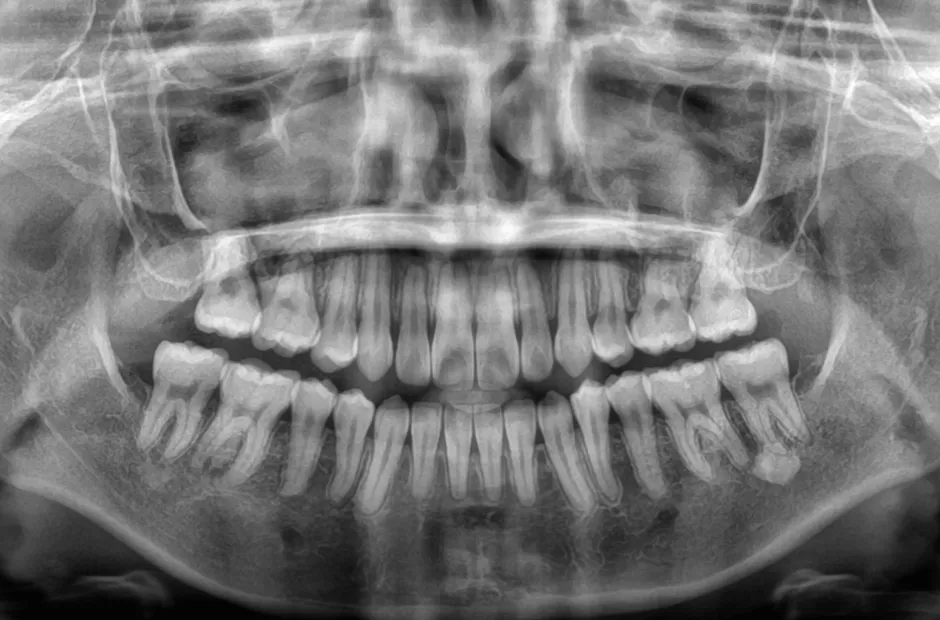

| 診断名・主訴 | 下顎前突、叢生 |

|---|---|

| 年齢・性別 | 23歳・女性 |

| 治療期間・回数 | 3年 |

| 治療に用いた主な装置 | 上顎5,5 下顎4,4 |

| 抜歯部位 | 舌側矯正 |

| 治療費 | 100万円(税抜) |

| リスク・副作用 | 装置による違和感・疼痛・歯肉退縮・歯根吸収・虫歯のリスクなど |

治療前

治療中

治療後